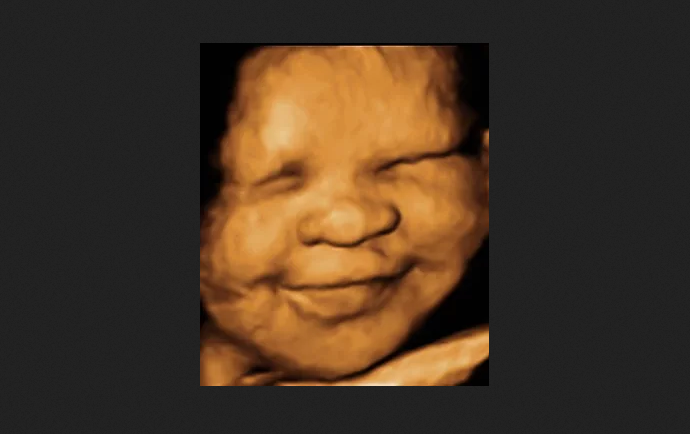

Texas Abortion Ban Goes To The Supreme CourtcortezrealnewsDec 17, 20211 min readSupreme Court Sends Texas Abortion Ban to Appeals Court, Will Likely be Upheld and Save More Babieshttps://www.lifenews.com/2021/12/16/supreme-court-sends-texas-abortion-ban-to-appeals-court-will-likely-be-upheld-and-save-more-babies/?fbclid=IwAR3AscWGY9mbXGTcn0JAMA-7VxknOfktoPVeOPegoZ7fmILnHGAaiubJzxA